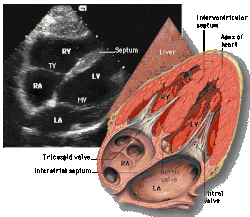

A transthoracic echocardiogram (TTE) is the most common type of echocardiogram, which is a still or moving image of the internal parts of the heart using ultrasound. In this case, the probe (or ultrasonic transducer) is placed on the chest or abdomen of the subject to get various views of the heart. It is used as a non-invasive assessment of the overall health of the heart, including a patient's heart valves and degree of heart muscle contraction (an indicator of the ejection fraction). The images are displayed on a monitor for real-time viewing and then recorded.

A TTE is a clinical tool to evaluate the structure and function of the heart. All four chambers and all four valves can be assessed by TTE, but the quality and visibility of these structures varies from person to person. Other structures visible on TTE include the aorta, the pericardium, pleural effusions, ascites, and inferior vena cava. It can be used to diagnose a heart attack, enlargement/hypertrophy of the heart, infiltration of the heart from an abnormal substance (e.g. amyloidosis), weakness of the heart, and cardiac tumors. With advanced measurements of the movement of the tissue with time (Tissue Doppler), it can measure diastolic function, fluid status,[1] and ventricular dyssynchrony.